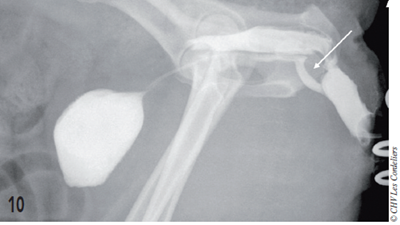

Figure 10 – Vaginouretrocystographie postopératoire après une TVT-O chez une chienne incontinente.

Comparé à la Figure 4, on note le « décoché » de l’urètre (flèche blanche), soutenu par la bandelette.